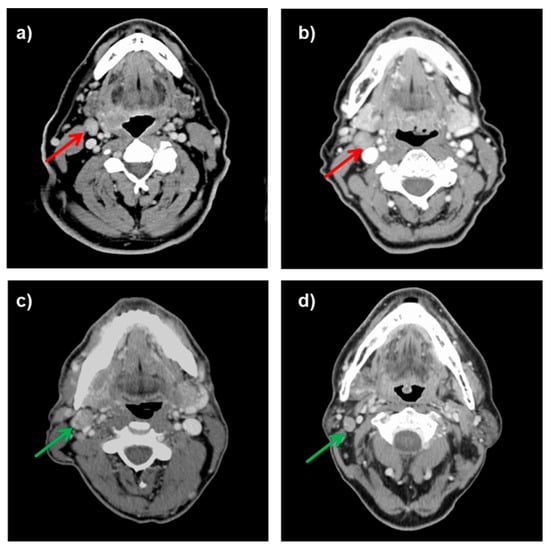

Figure 1.

Axial contrast-enhanced CT scans of HNC patients clinically staged as neck lymph node positive who were histopathologically negative and who could be rejected from postoperative irradiation (upper row). In the lower row, CT scans of patients who were actually histopathologically positive and who had postoperative irradiation (lower row). Red arrow indicates cervical lymph node overstaging. Green arrow indicates true positive lymph node staging: (a) A 62-year-old male patient with a cT2cN2bcM0 oropharyngeal cancer treated with lateral pharyngotomy and neck dissection; (b) A 61-year-old female patient with a cT2cN2bcM0 supraglottic laryngeal cancer treated with transoral resection and neck dissection; (c) A 54-year-old male patient with a cT2cN2bM0 (pT2pN1) oropharyngeal cancer treated with transoral resection, neck dissection and PORT; (d) A 57-year-old male patient with a cT2cN2cM0 (pT2pN2c) supraglottic laryngeal cancer treated with transoral resection, bilateral neck dissection and PORT.